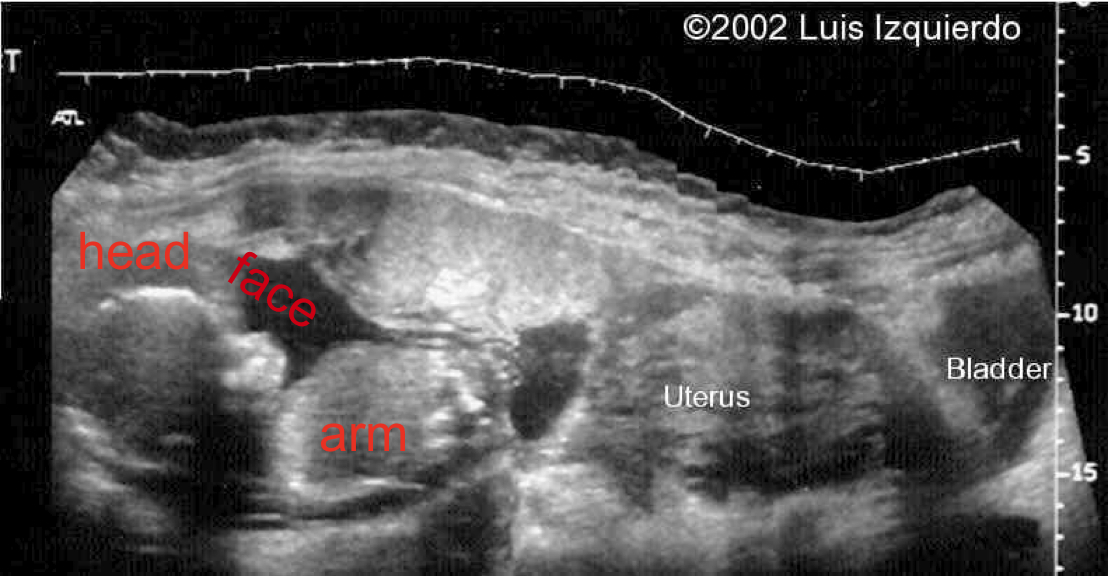

Now you might think that once an egg has fallen into the abdomen, its chances of survival are nil. Surprisingly, at the appropriate time of development, an embryo can implant itself into almost any living tissue that it happens to alight upon. And the abdomen is filled with all sorts of tissues – from the intestines to the kidney, to the liver and the spleen. With successful implantation and sufficient placental formation, the embryo can develop normally into a fetus that can be carried through a full nine months of pregnancy. At the end, of course, it has nowhere to go unless it’s delivered by a modified Cesarian Section. The medical literature is filled with sporadic reports of healthy live-born babies that were carried by mothers pregnant in this unusual way. Here's an amazing picture of a late-state pregnant woman on her belly with a fetus facing up.